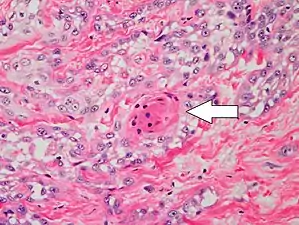

Histopathologically, the epidermis in cSCC in situ (Bowen's disease) will show hyperkeratosis and parakeratosis. There will also be marked acanthosis with elongation and thickening of the rete ridges. These changes will overly keratinocytic cells which are often highly atypical and may in fact have a more unusual appearance than invasive cSCC. The atypia spans the full thickness of the epidermis, with the keratinocytes demonstrating intense mitotic activity, pleomorphism, and greatly enlarged nuclei. They will also show a loss of maturity and polarity, giving the epidermis a disordered or "windblown" appearance.

Two types of multinucleated cells may be seen: the first will present as a multinucleated giant cell, and the second will appear as a dyskeratotic cell engulfed in the cytoplasm of a keratinocyte. Occasionally, cells of the upper epidermis will undergo vacuolization, demonstrating an abundant and strongly eosinophilic cytoplasm. There may be a mild to moderate lymphohistiocytic infiltrate detected in the upper dermis.[12]